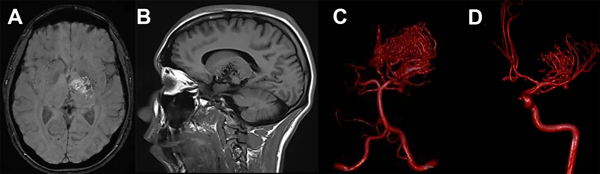

Figura 4: A) MAV Tálamo-capsular izquierda Grado III B. B) Corte sagital de RMN donde se ve el nido intratalámico. C) Aferencias dependientes del sistema tálamo-geniculadas posteriores. D)Aferencias dependientes del sistema lentículo estriado anterior.